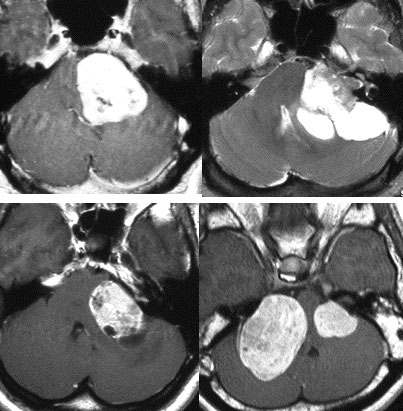

聴神経腫瘍でまず手術が必要なのは巨大なものです。この4枚の写真は私が実際に手術をした患者さんのものです。脳幹部という脳の最も大切なところが腫瘍によって圧迫されて変形しているのが特徴です。右上のものはのう胞性腫瘍なので大きさの割に手術のリスクは高くありませんが,左上のものは実質性で出血性のものですごくリスクが高い手術でした。左下のものは普通のリスク。右下のものは超高難易度のものです。